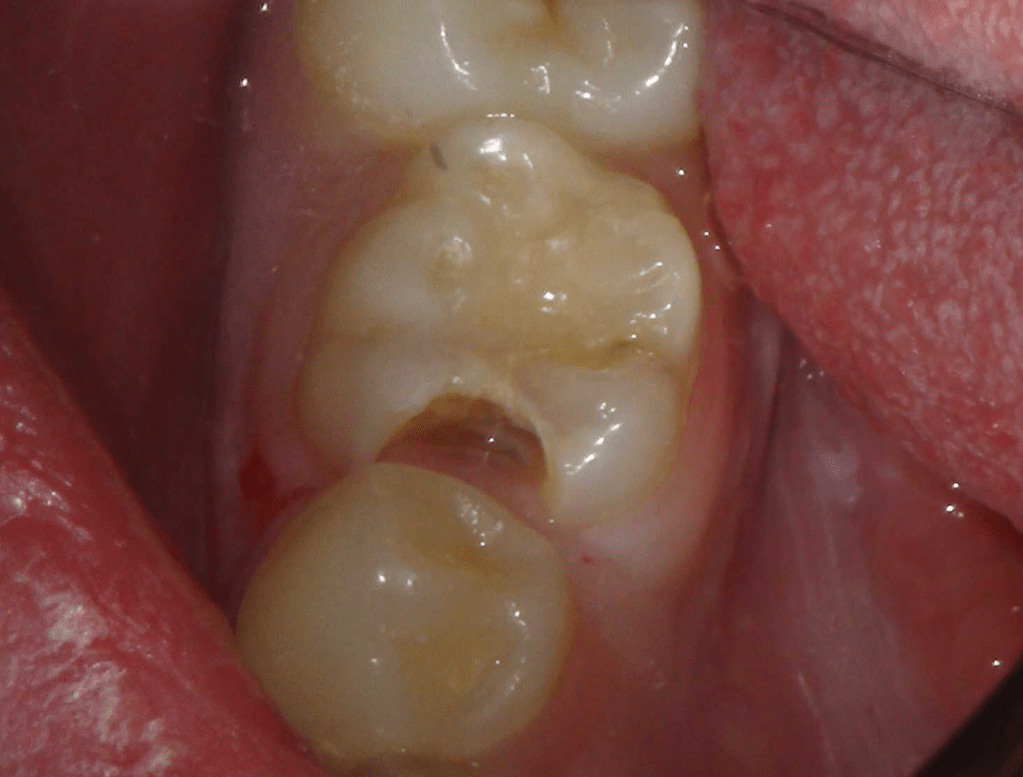

Reco pre-endo, molar inferior